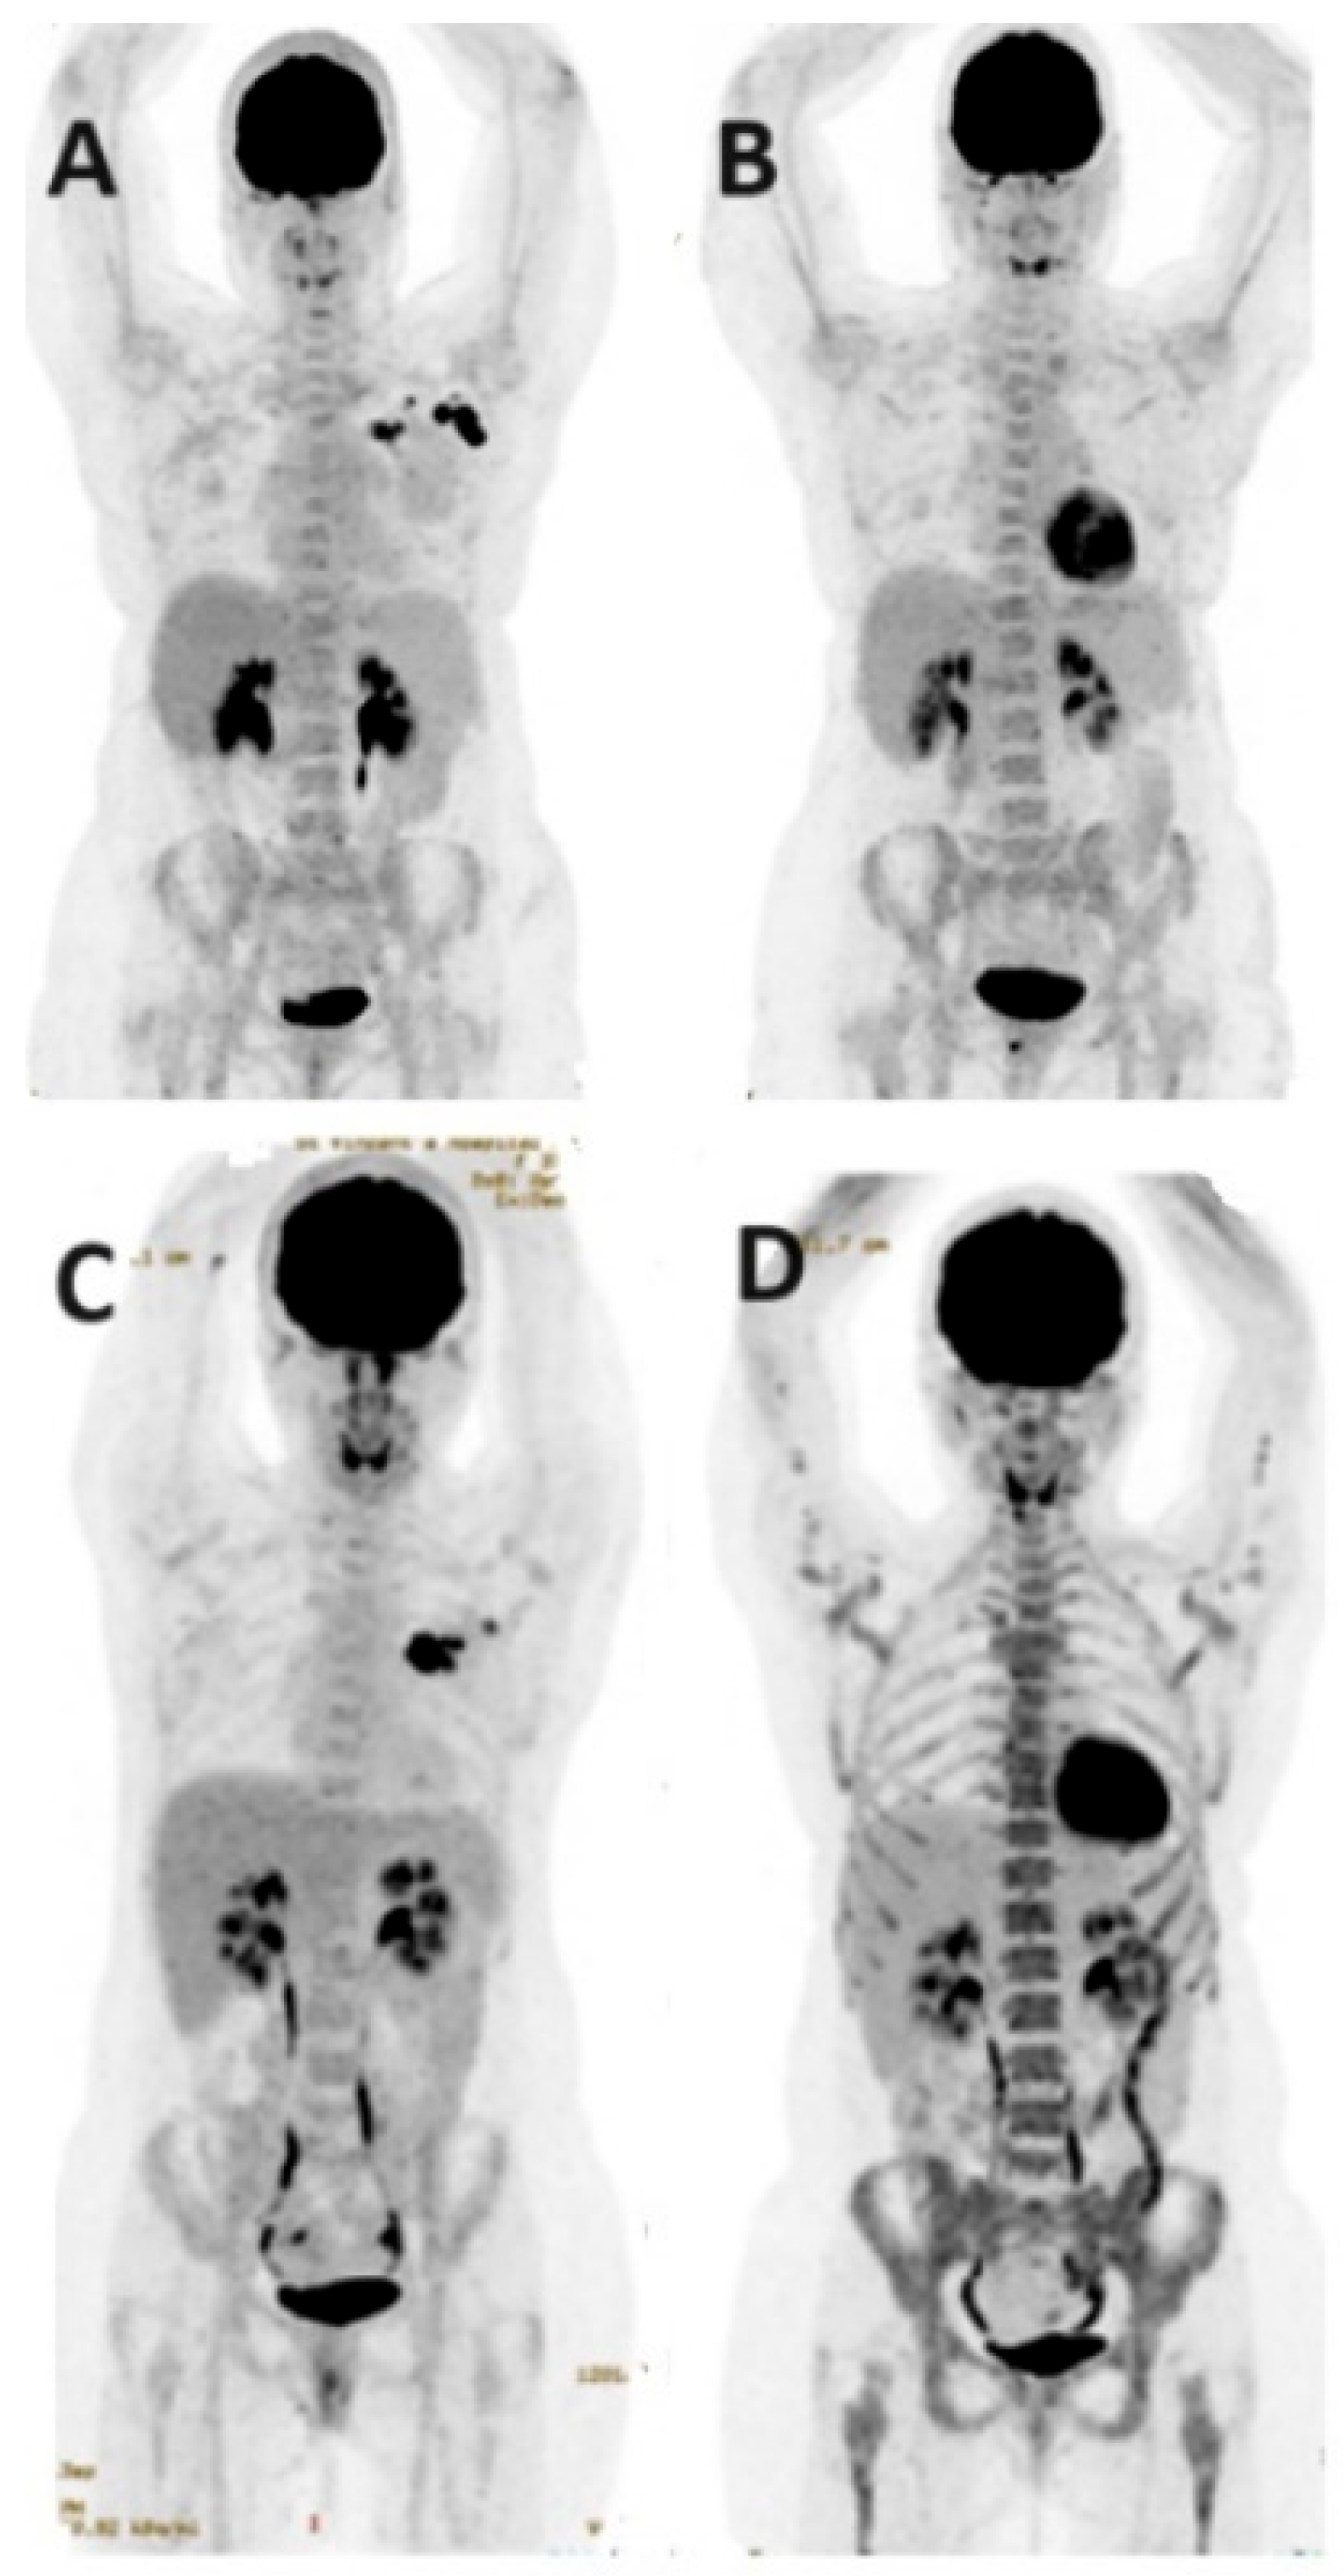

- Venema, C.M.; Mammatas, L.H.; Schröder, C.P.; Van Kruchten, M.; Apollonio, G.; Glaudemans, A.W.J.M.; Bongaerts, A.H.; Hoekstra, O.S.; Verheul, H.M.; Boven, E.; et al. Androgen and Estrogen Receptor Imaging in Metastatic Breast Cancer Patients as a Surrogate for Tissue Biopsies. J. Nucl. Med. 2017, 58, 1906–1912. [Google Scholar] [CrossRef] [PubMed]

- Jacene, H.; Liu, M.; Cheng, S.C.; Abbott, A.; Dubey, S.; McCall, K.; Young, D.; Johnston, M.; Abbeele, A.D.V.D.; Overmoyer, B. Imaging Androgen Receptors in Breast Cancer with 18F-Fluoro-5α-Dihydrotestosterone PET: A Pilot Study. J. Nucl. Med. 2022, 63, 22–28. [Google Scholar] [CrossRef] [PubMed]